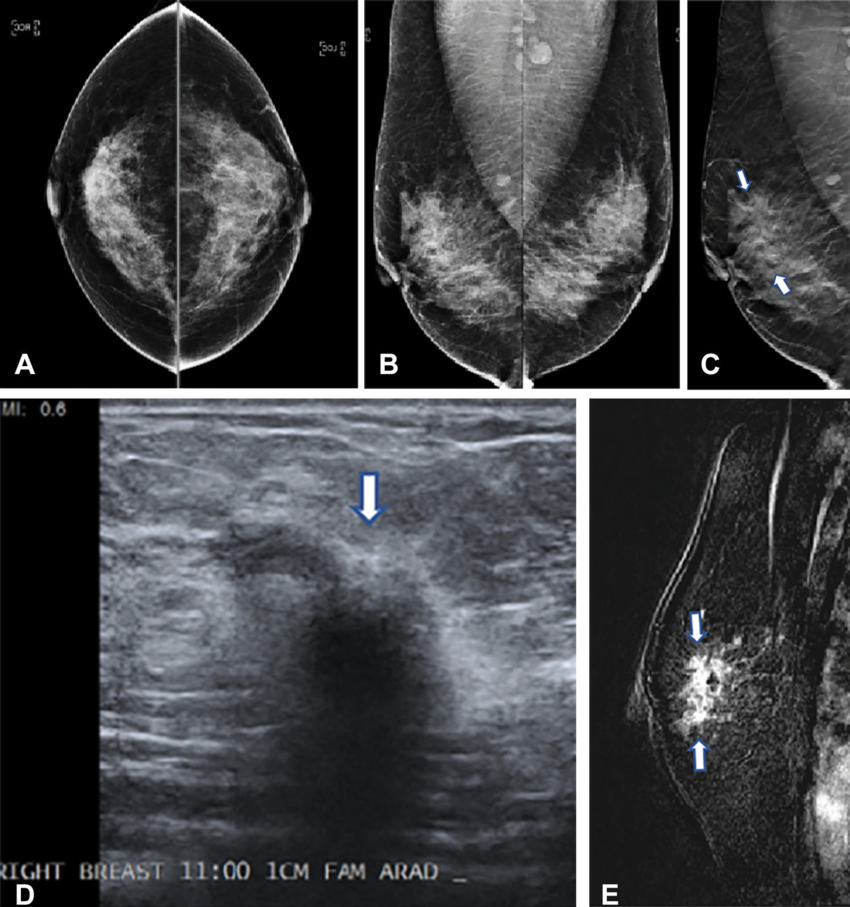

Figure 2. Images in a 42-year-old woman who presented for routine screening. (A) Two-dimensional craniocaudal digital mammogram and (B) two-dimensional mediolateral digital mammogram show heterogeneously dense breast tissue with no abnormality. (C) Mediolateral digital breast tomosynthesis image shows subtle architectural distortion (arrows) extending superiorly from the nipple level. (D) Target US image of the right breast shows a highly suspicious, hypoechoic, irregular mass (arrow). US-guided core biopsy yielded invasive ductal carcinoma with extensive ductal carcinoma in situ (T2N0M0; estrogen receptor–positive, progesterone receptor–positive, and human epidermal growth factor receptor 2–negative). (E) Right-breast MRI scan acquired to evaluate the extent of disease shows a clip artifact in the superior aspect of the irregular enhancing mass (arrows). No other suspicious lesions were seen.

High-res (TIF) version